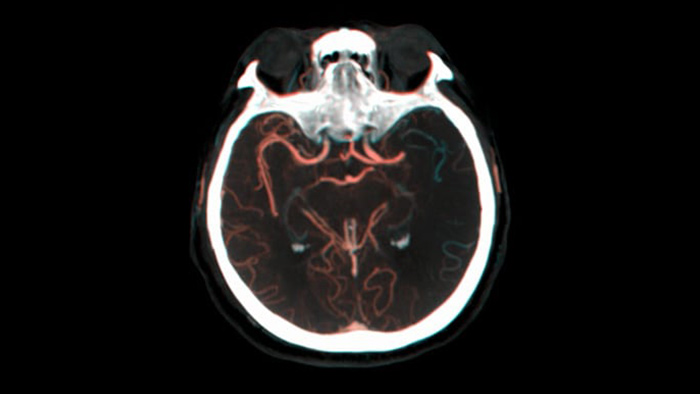

SmartCT Vaso permet de visualiser au-delà du caillot grâce à l’imagerie péri-procédurale de l’aspect des vaisseaux distaux dans les accidents vasculaires cérébraux ischémiques. SmartCT Vaso est une technique basée sur une acquisition Cone Beam CT à faisceau conique et une injection de produit de contraste intra-artérielle. Elle permet la visualisation au-delà du caillot avec l’imagerie péri-procédurale de l’aspect des vaisseaux distaux dans l’accident vasculaire cérébral ischémique. Grâce au remplissage rétrograde, les structures des vaisseaux avant et après le caillot deviennent visibles. SmartCT Vaso 3D Roadmap vous aide à visualiser les dispositifs de retrait de caillot.

SmartCT Roadmap fournit des références anatomiques permettant une navigation précise du fil-guide, du cathéter et du dispositif jusqu’au caillot.